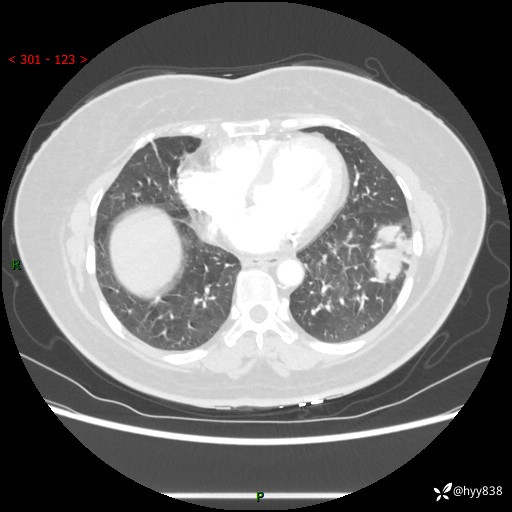

【现病史及既往史】:患者自诉2月前体检发现肺结节(左肺下叶约17mm,右肺上叶4mm),未予特殊处理,2024-10-12当地市第五医院门诊复查胸部CT提示右下肺结节(大小约3.3cm*3.9cm),患者无咳嗽、咳痰,无畏寒、发热、盗汗,无咯血,无胸闷、胸痛、呼吸困难,无恶心、呕吐,无腹痛、腹胀、腹泻等不适,现为求进一步诊治,门诊以“孤立性肺结节”收住我科。 患者本次起病来精神、食欲、睡眠尚可,大小便正常,体力、体重无明显变化。

【检查】:胸部CT增强检查